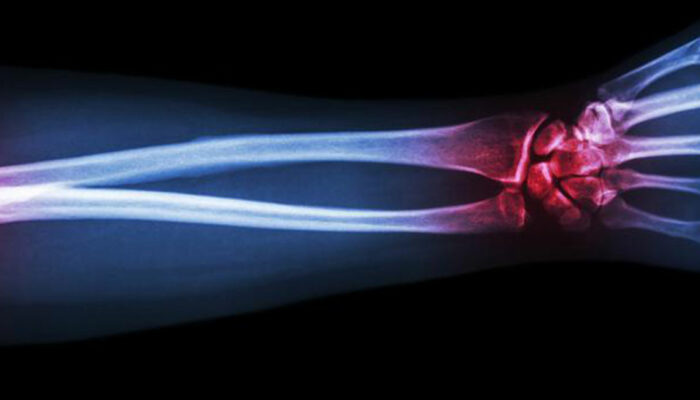

Gout is a type of arthritis that primarily attacks the joints and other body parts like the ears, wrists, knuckles, knee, ankles, and other small joints. It is often characterized by painful swelling, stiffness, and inflammation of these affected joints. The swelling and stiffness are mainly the results of excess levels of uric acid forming crystals in the joints.

After doing a thorough physical exam, the doctor may also take a sample of the fluid from the swelling of the joint to look for uric acid crystals. A blood test is also needed to know the levels of uric acid in your bloodstream.